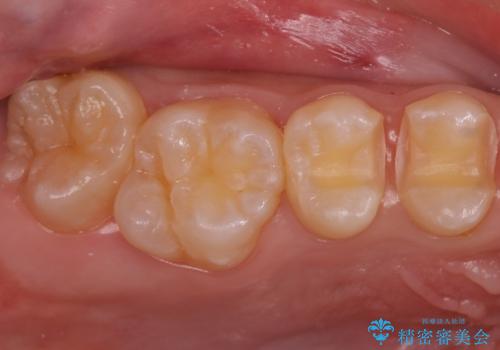

歯と歯の間の虫歯 セラミックインレーでの治療

- 検査の結果奥歯と奥歯の間に虫歯が確認されました。

虫歯を取り除いた後、セラミックインレーで修復していきます。

- 右上45 セラミックインレー 77,000円×2本費用は治療当時の料金となります